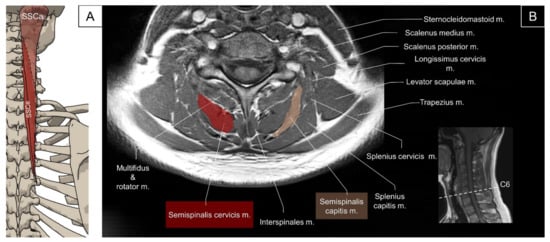

4.3. Transversospinalis (Semispinalis Capitis/Semispinalis Cervicis/Multifidus)

4.3.1. Anatomy

4.3.2. Sonographic Scanning

4.3.3. Clinical Relevance